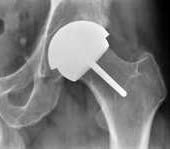

جراحة تغطية سطح مفصل الفخذ

هذه الجراحة كانت تستخدم لعلاج بعض حالات خشونة مفصل الفخذ في المرضى الغير متقدمين فى السن (أقل من 50 سنة). وفي هذه الجراحة، لا يتم إزالة رأس عظمة الفخذ (كما يحدث فى التغيير الكامل لمفصل الفخذ) بل يتم تشكيل رأس العظمة ليتم تغطيتها بجزء معدني على شكل نصف كرة. كما يتم أيضا تركيب بطانة معدنية لحق المفصل.

وتتطلب هذه الجراحة ألا يكون هناك تشوها كبيرا لعظام مفصل الفخذ.

مزايا هذه الجراحة:

- لا يتم إزالة رأس عظمة الفخذ ولا يتم فتح القناة النخاعية للعظمة، وبالتالي لا يوجد نقص فى العظام إذا إحتاج المريض لإعادة تركيب مفصل فخذ كامل بعد عدة سنين.

- إنخفاض إحتمال حدوث خلع بالمفصل بعد الجراحة.

- لا يوجد جزء بلاستيكي قد يحدث به تآكل.

عيوب الجراحة:

- نسبة صغيرة من المرضى يحدث لهم كسر فى عنق عظمة الفخذ.

- أحتكاك الأسطح المعدنية مع بعضها يزيد من نسبة المعادن فى الدم. وهذا قد يكون له تأثير سيء على الجسم.

- لا تصلح مع الحالات التى بها تشوه كبير فى عظام مفصل الفخذ أو فى حالات هشاشة العظام.

- لا تصلح للسيدات فى عمر الحمل لأن نسبة المعادن فى الدم قد يكون لها تأثير على الجنين.

لذا فقد توقف اغلب الجراحين حول العالم عن إستخدام هذه الطريقة للعلاج، والإكتفاء بالمفاصل الصناعية التقليدية.